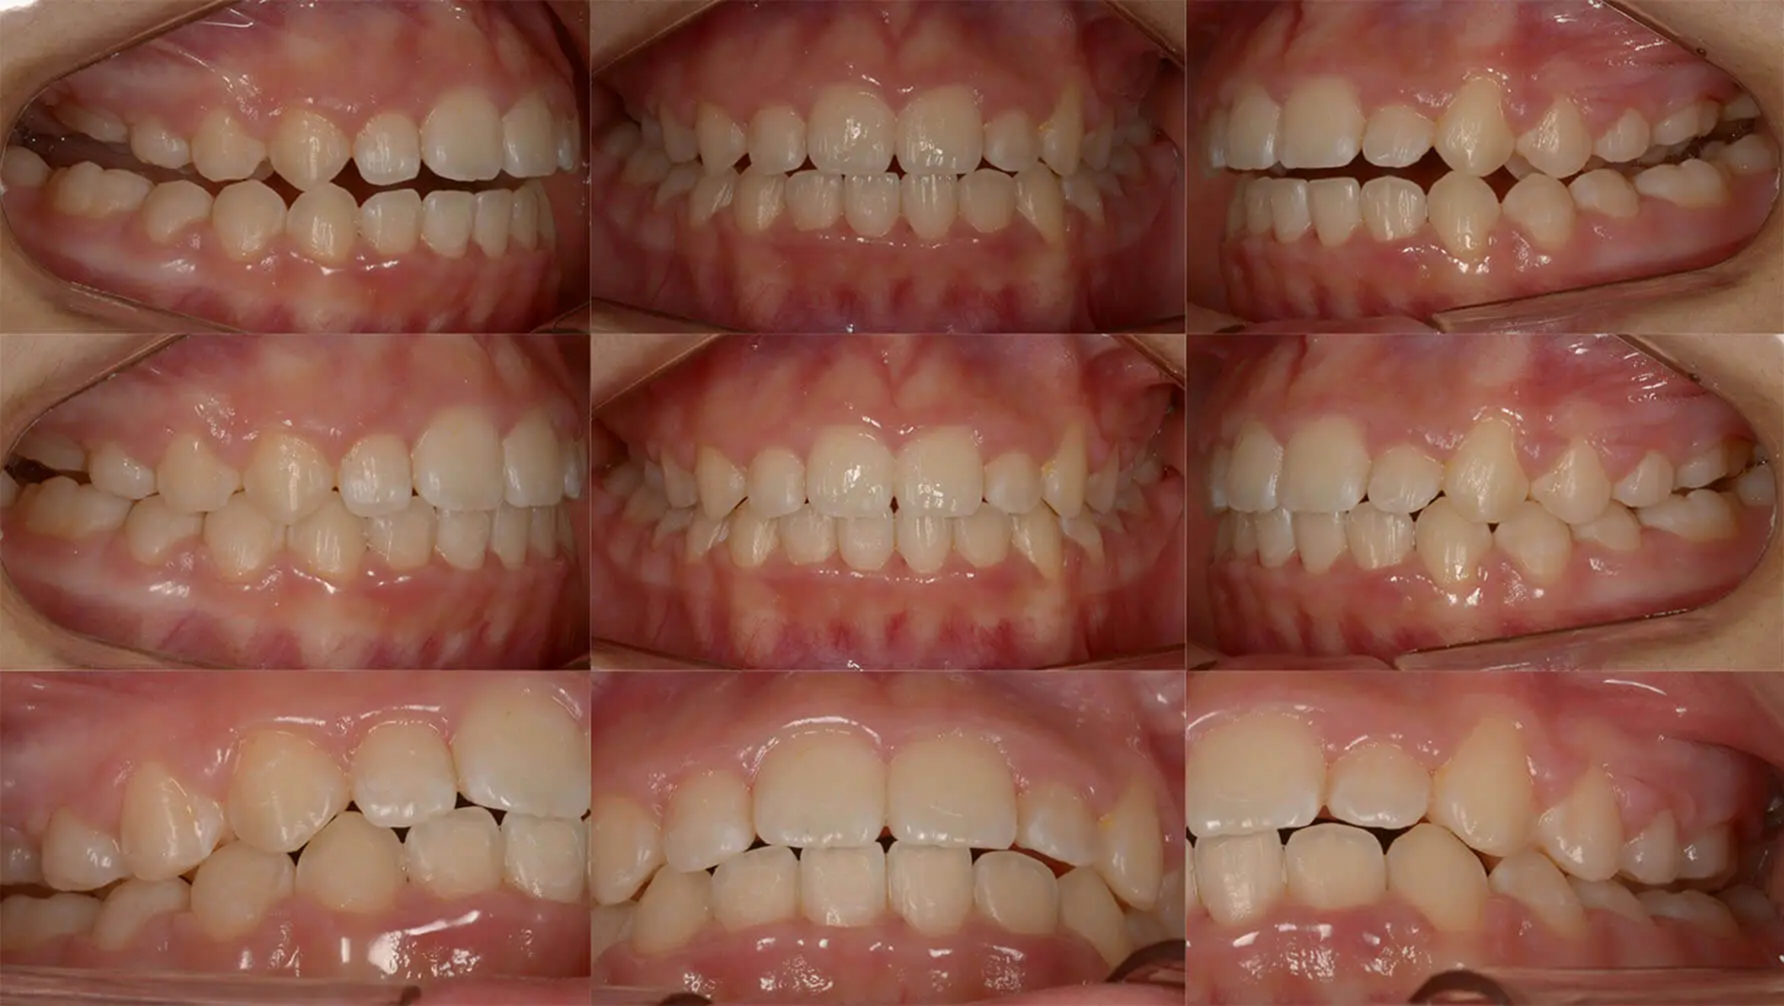

Case02凸凹とを歯を抜かずに改善した症例

全体的な歯列不正が著しく、ブラッシングがしにくい状態でした。永久歯の異所萌出により両側上顎乳犬歯は晩期残存していました。診査の結果、歯列の狭窄を認めたため、オーバーレイアーチによる拡大を行えば、抜歯なしで矯正できると診断しました。かなり窮屈な部位もありましたが、きれいに歯列を整えました。むし歯治療も適正に行い、審美的な状態を獲得しました。

初診 2017.5.16

矯正治療開始 2017.8.7

ファイナル 2018.11.13

| 主訴 | 全体的な凸凹をきれいにしたい |

|---|---|

| 診断 | 両側アングル1級の叢生 |

| 矯正方法 | オーバーレイアーチを用いたマルチブラケット |

| 矯正期間 | 13か月・15回 |

| 費用 | 710,000円(税別) |

| 調整料 | 月1回 5,000円(税別) |